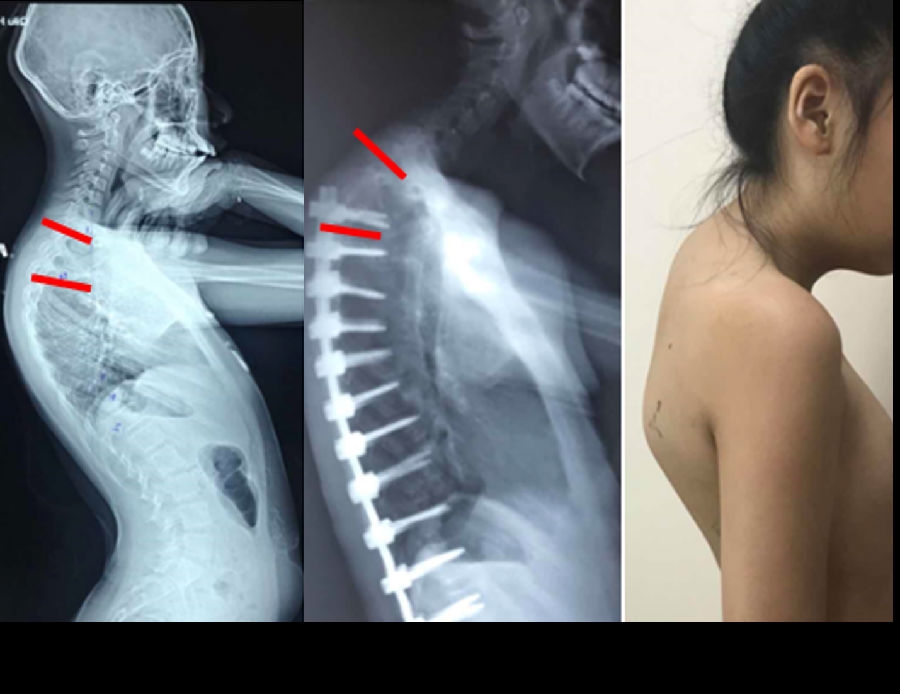

(2)上固定椎在交界区或存在交界性后凸

图6 长节段融合固定上固定椎(UIV)选择在胸10-12胸腰椎交界区是PJK的风险因素之一

(3)上固定椎位于T1-3

图7 术前-术后1个月-术后1个月外观